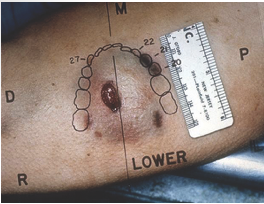

location

distribution

presence of satellite injuries

characteristics: length, shape, orientation, appearance of margins, marginal or adjacent abrasion, depth and structures injured, direction of wound track

List the important factors to document for stab wound injuries (6)

close range gunshot wound

almost always circular

inverted edges

collar of abrasion

burning effects

tattooing/stippling